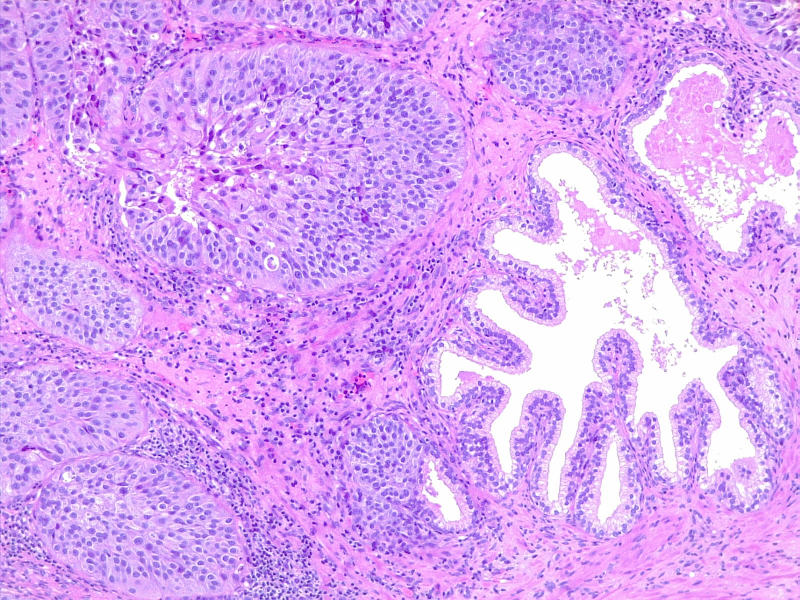

Urothelial carcinoma in situ in the setting of cystitis cystica et glandularis

圖2:膀胱炎和腺體的原位尿路上皮癌。由維基媒體 CoRus13 提供(公共領(lǐng)域 https://creativecommons.org/publicdomain/zero/1.0/deed.en)